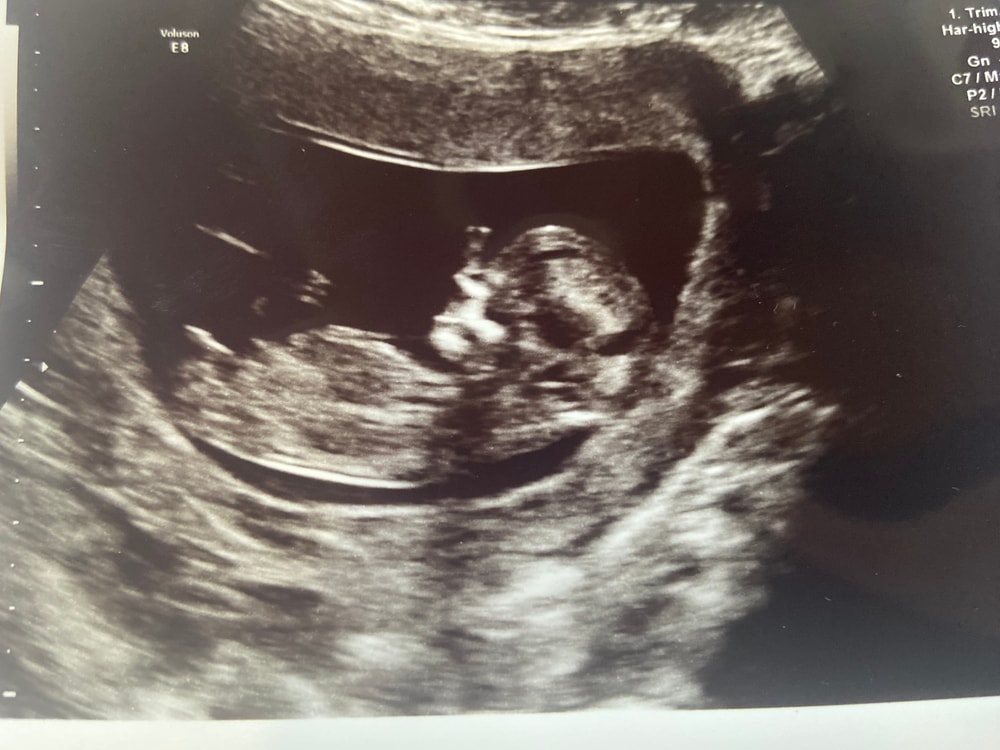

Пол ребёнка в 12 недель

Анализы, скринингиИнтересно, кто живет в домике. Поверила бы врачу, но была на двух узи с разницей в 1 день - и оба специалиста назвали разный пол. 1 говорит - 99 % мальчик, 2 говорит - 99 % девочка.

Мне кажется, что девочка. Половой бугорок как будто прям сильно горизонтальный.

Мама Львенка, как мне объяснил врач, у них у всех сейчас пипирки. Но разница в наклоне, может он постоянно меняется, я не знаю 🤣